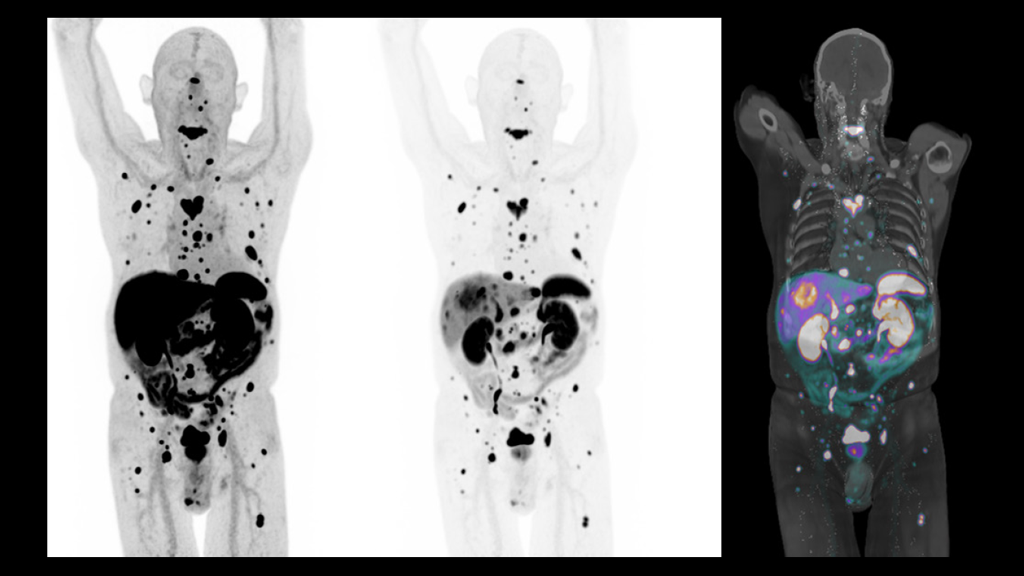

Automated Lesion Segmentation in WholeBody FDGPET/CT Challenge What Is A Tumor Imaging Pet Scan A positron emission tomography (pet) scan is an advanced nuclear imaging technique used to look for cancer and its. The scan uses a special dye containing. Pet stands for positron emission tomography. A pet scan is a test that creates 3 dimensional (3d) pictures of the inside of your body. A positron emission tomography (pet) scan uses a safe injectable. What Is A Tumor Imaging Pet Scan.

Totalbody dynamic PET successfully detects metastatic cancer; first What Is A Tumor Imaging Pet Scan A pet scan is a test that creates 3 dimensional (3d) pictures of the inside of your body. When is a pet scan used? A pet (positron emission tomography) scan is a type of imaging test that is used to diagnose certain diseases including cancer. The scan uses a special dye containing. A positron emission tomography (pet) scan is an. What Is A Tumor Imaging Pet Scan.